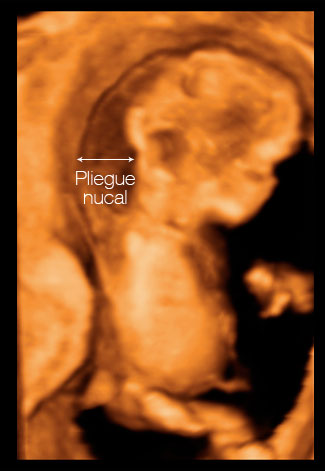

Ecografías de la semana 12: El pliegue nucal

Se trata de un acúmulo de líquido que se localiza en la parte posterior del cuello y dorso fetal. Este acúmulo de líquido existe en todos los fetos, pero es mayor en los que tienen síndrome de Down u otras alteraciones cromosómicas. También se ha visto que puede estar aumentado en fetos con otras alteraciones, cardiacas, como ejemplo [ Ver ecografía del pliegue nucal ]